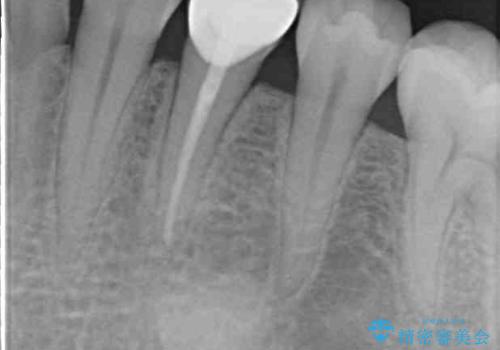

レントゲン写真などで診査を行ったところ、左下の第一小臼歯の神経組織が壊死し、根尖部周辺の骨に炎症が認められました。

根管治療後6ヶ月でレントゲン写真を撮影したところ、根尖部周辺の炎症が消退していることが認められました。